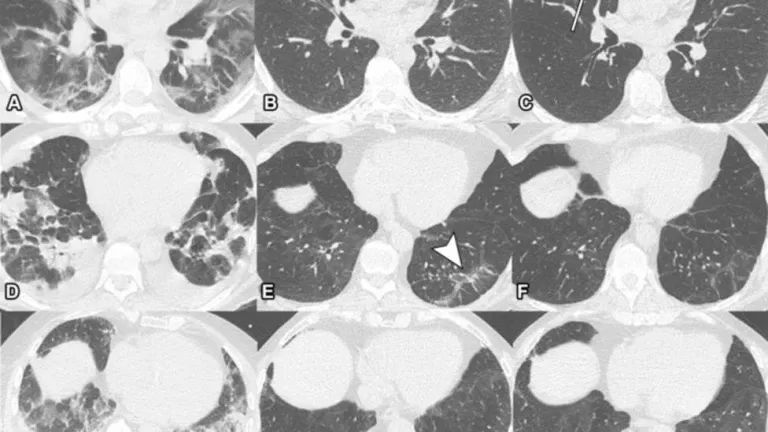

Las autoridades sanitarias de la provincia argentina de Tucumán (norte) confirmaron este sábado el fallecimiento de una cuarta víctima por brote de neumonía bilateral de origen desconocido, que fue detectado por primera vez en un sanatorio privado.

“El Ministerio de Salud Pública informa el fallecimiento de un paciente vinculado al conglomerado de casos de neumonía de origen desconocido. Se trata de un paciente del sexo masculino de 48 años de edad, con comorbilidades, que se encontraba internado en grave estado en el sector público”, indicó la cartera provincial en un comunicado oficial.

Por otra parte, el número de personas infectadas se incrementó a once luego de que se detectara un nuevo caso a un hombre de 64 años con comorbilidades, que está internado en grave estado con asistencia respiratoria mecánica, en hospital del sector privado.